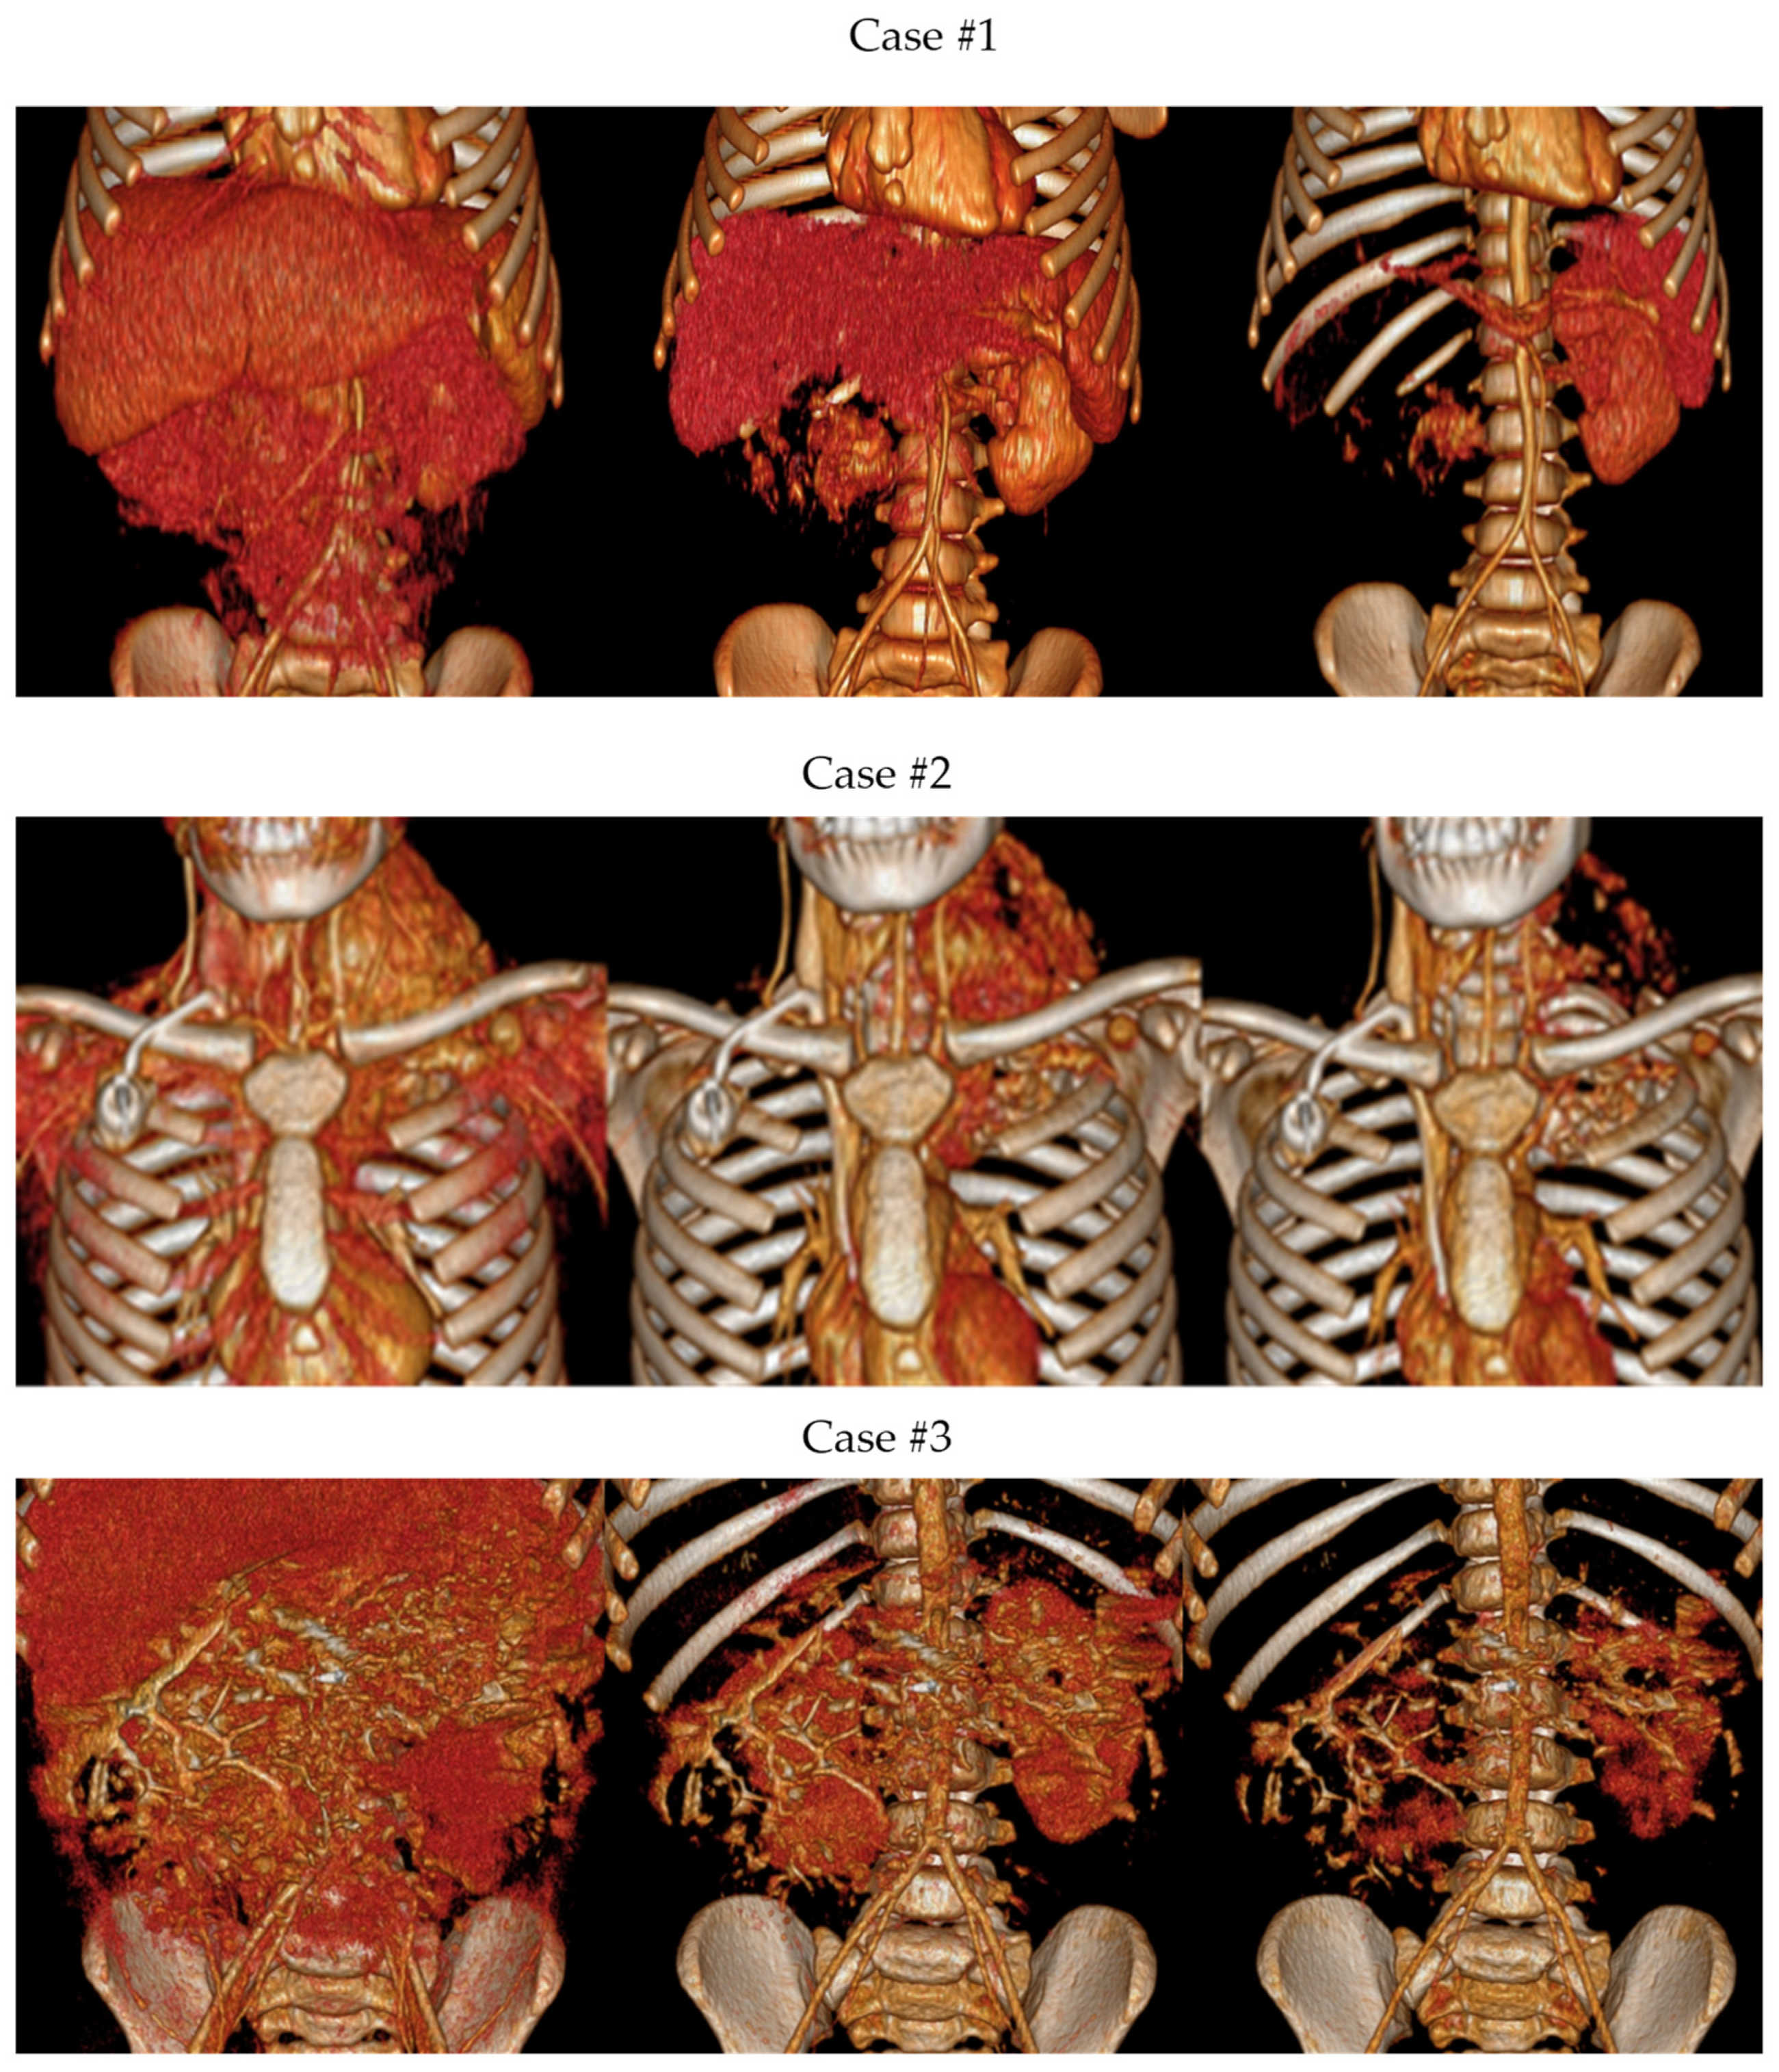

3.1.2. Volume Rendering and Cinematic Rendering